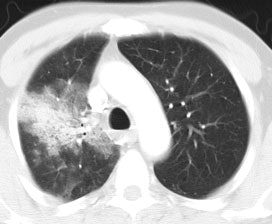

Bronchoalveolar cell carcinoma (BAC): The images below were from a patient with bronchoalveolar cell carcinoma that presented as a chronic right lung infiltrate. The FDG PET exam was positive in this case despite a higher likelihood of a false negative exams in patients with BAC. Note the most intense area of FDG accumulation corresponds to the area of greatest consolidation on CT imaging. |